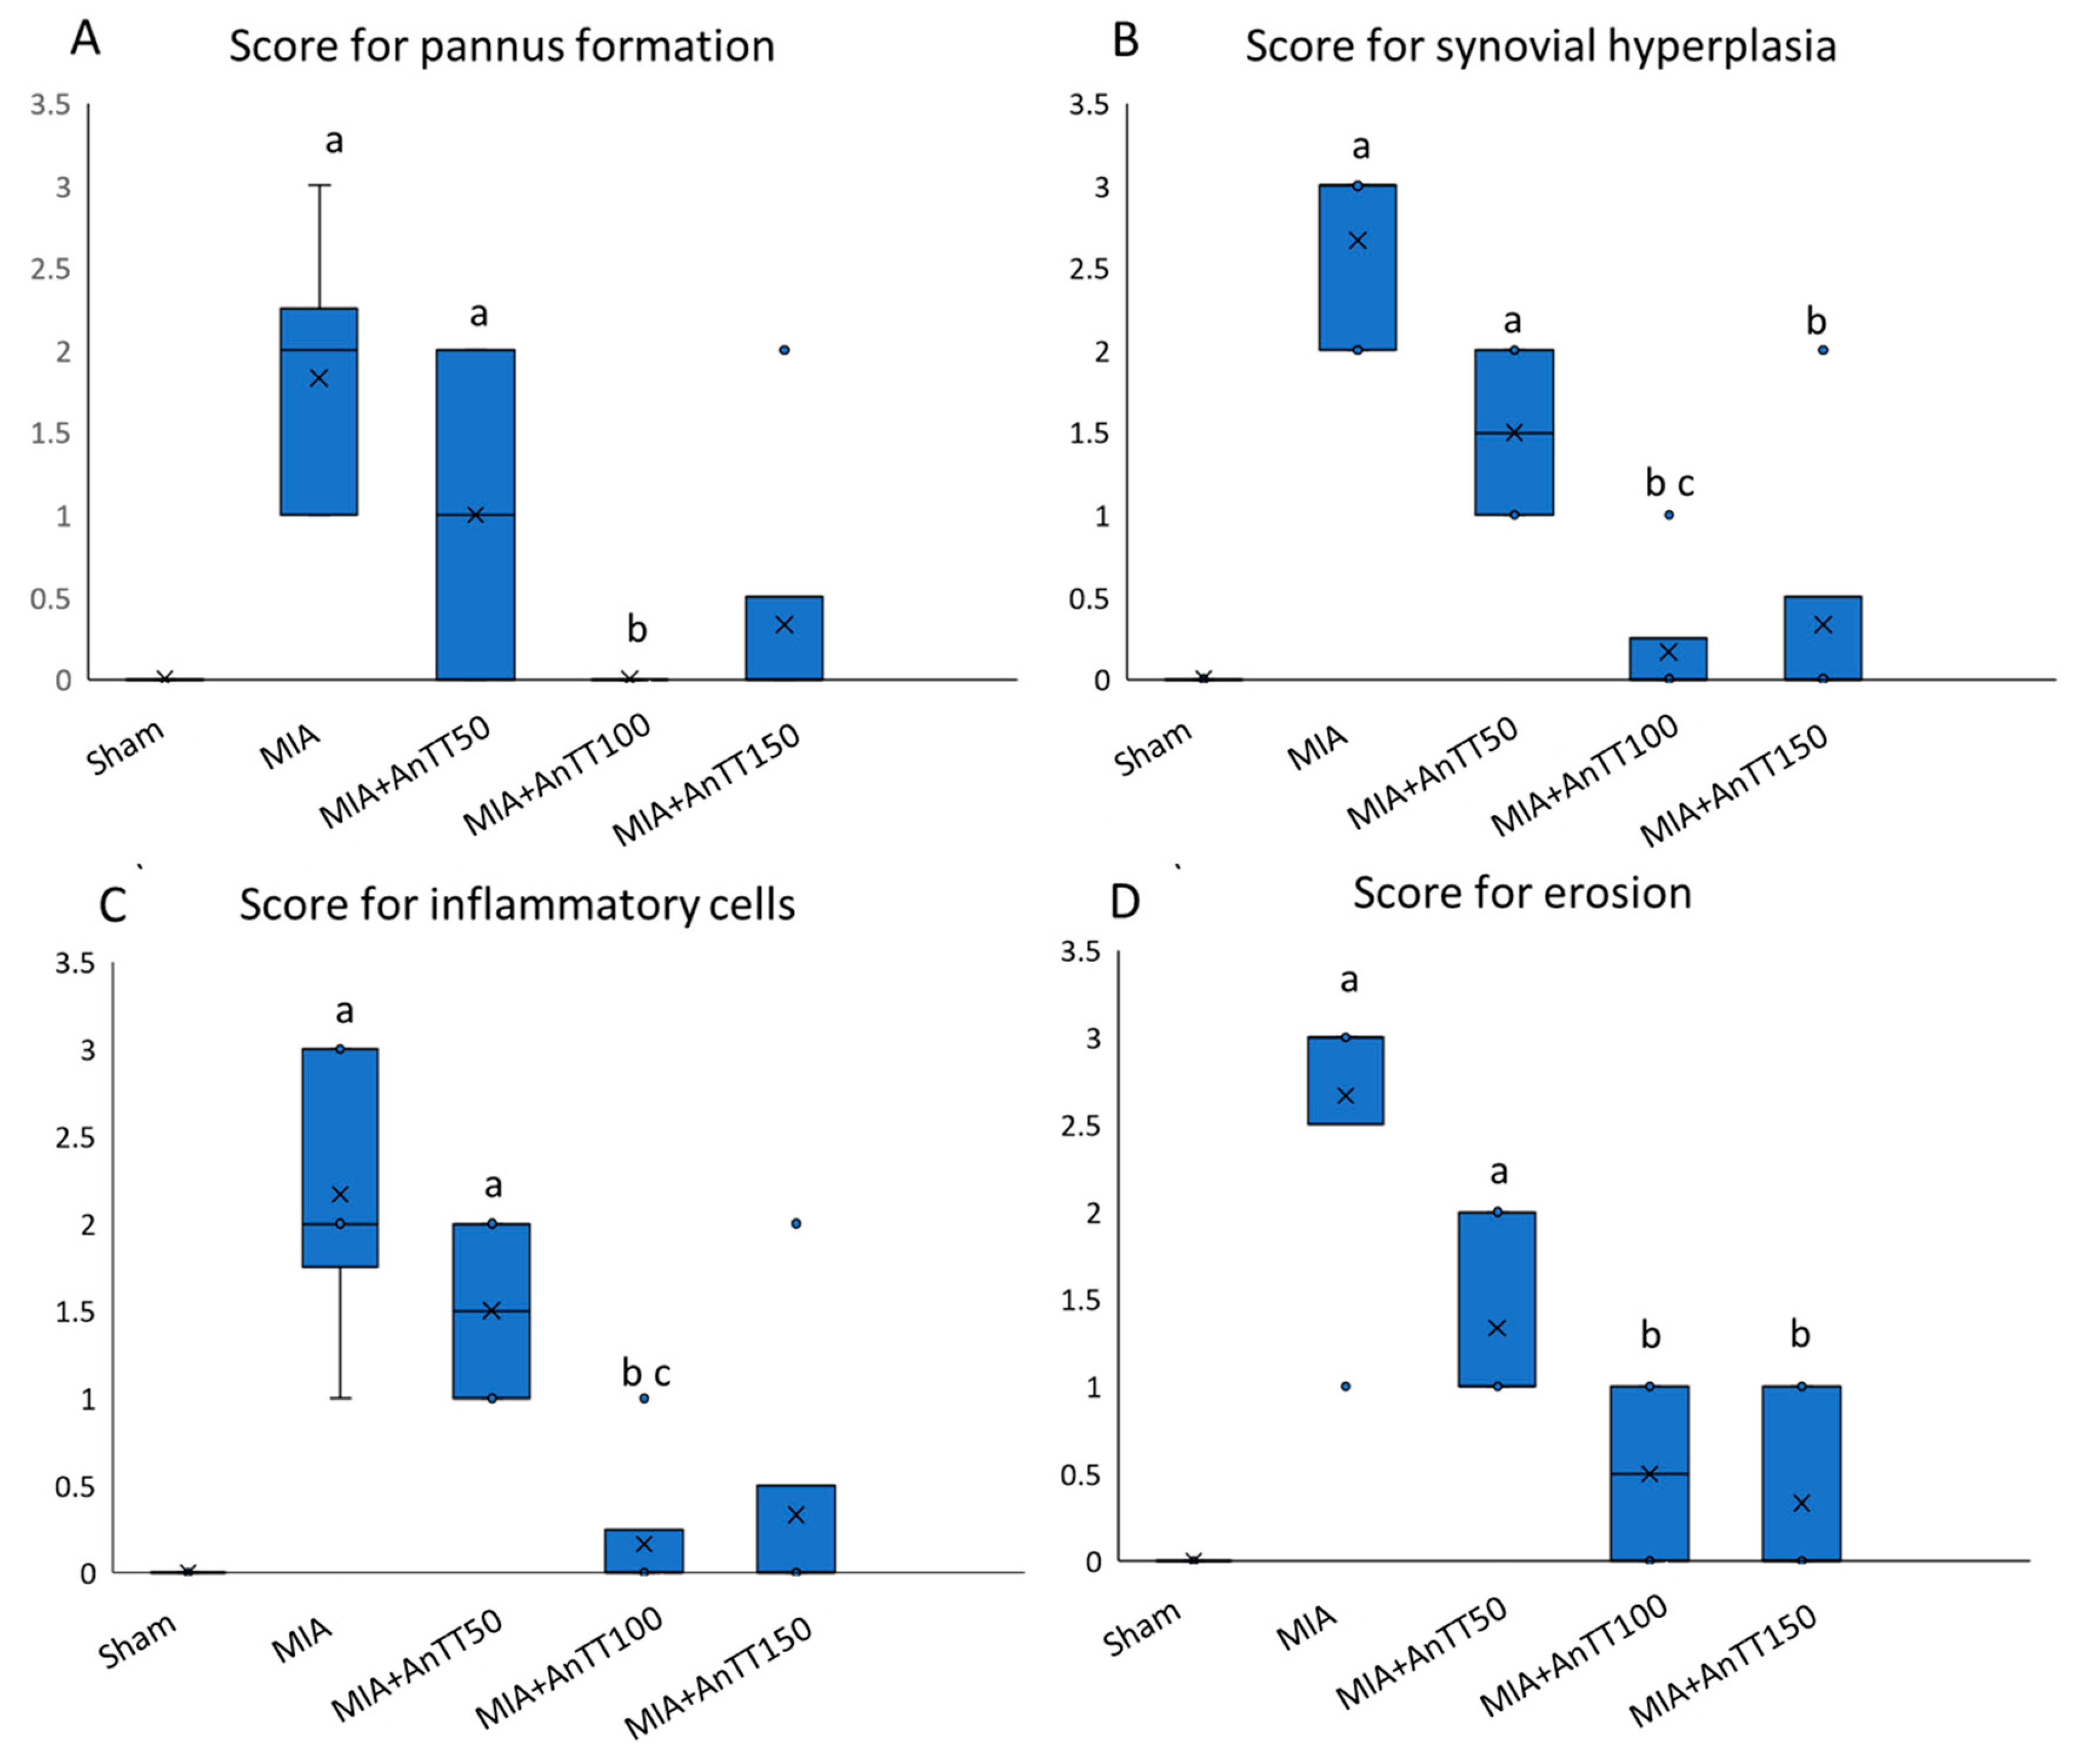

2.3. Histological Analysis

3. Results

4. Discussion